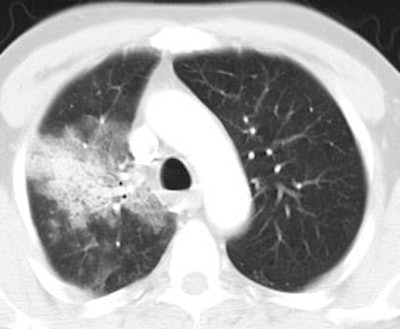

False positive PET scan: The patient below had a right middle lobe nodule detected incidentally during abdominal CT scanning. The nodule demonstrated increased FDG uptake on PET imaging. Due to a history of chemical exposure and second hand smoke inhalation the nodule was resected and found to be a granuloma. |

|